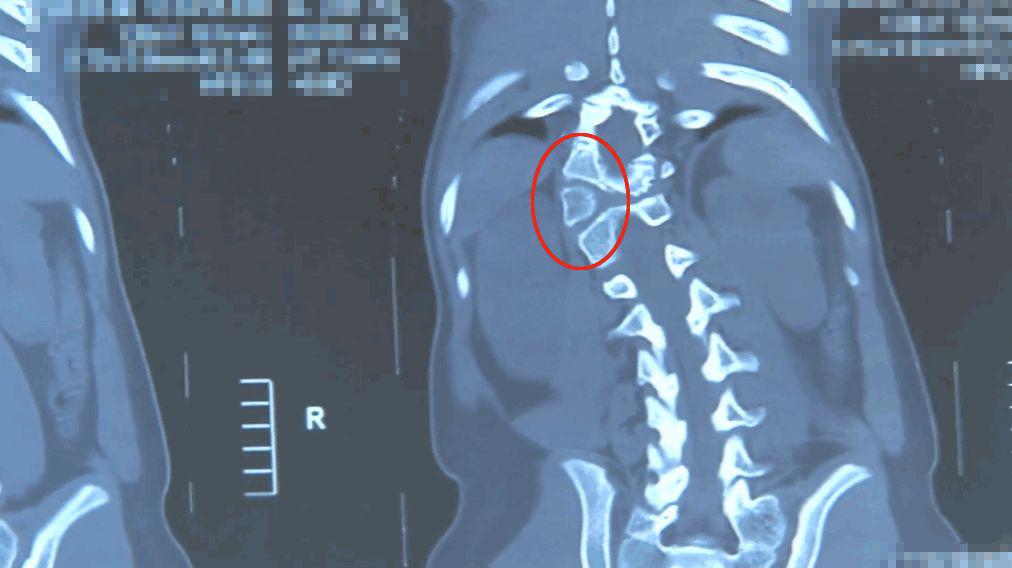

脊柱側彎,即脊柱向側方彎曲——正常人的脊柱從正面看是直的,而脊柱側彎患者的脊柱從正面看是呈字母「C」形或者「S」形的。

由于人體的脊柱是三維結構,從三維上看,脊柱側彎會伴有脊柱結構的旋轉,是一種三維的脊柱畸形。

半椎體切除術,是目前治療半椎體畸形最理想的方法。

但手術操作復雜,稍有差池就可能傷及神經,和田醫院不具備作這種手術的條件,保證不了塔吉的安全。